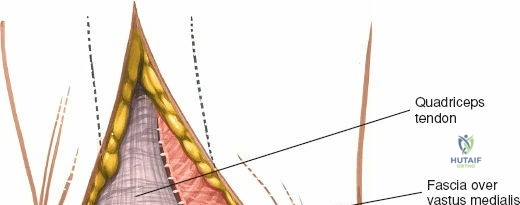

The extensor mechanism comprises the quadriceps femoris muscle group, the quadriceps tendon, the patella, the patellar tendon (ligament), and its insertion into the tibial tubercle.

* Quadriceps Tendon: The confluence of the rectus femoris, vastus lateralis, vastus medialis, and vastus intermedius. The medial parapatellar approach involves an incision extending into the medial aspect of the quadriceps tendon or a separation between the vastus medialis and rectus femoris.

* The incision through the joint capsule and retinaculum begins proximally, extending through the medial aspect of the quadriceps tendon.

6. Internervous Planes & Tissue Handling

* Quadriceps Tendon: The proximal extension of the arthrotomy enters the quadriceps tendon. A limited "quadriceps snip" can aid in patellar eversion without significantly weakening the tendon.

Proximal extension of the arthrotomy, showing incision into the quadriceps tendon to facilitate further exposure.